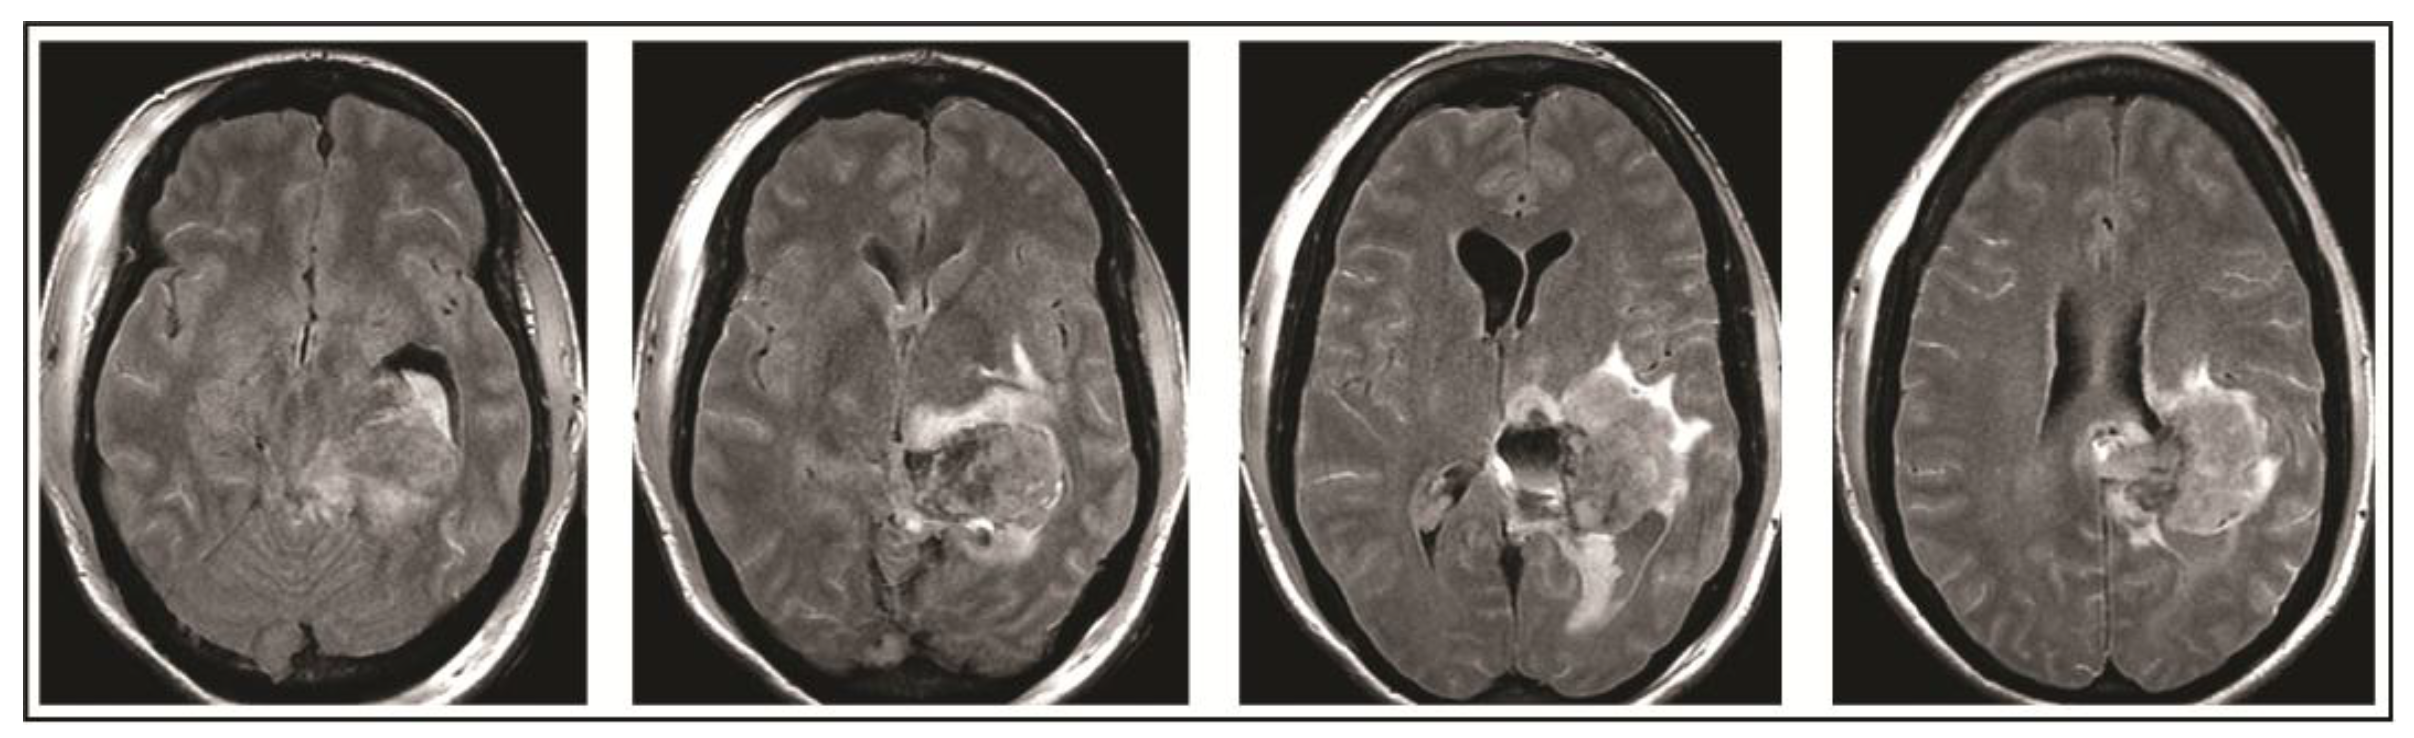

2. Case Presentation